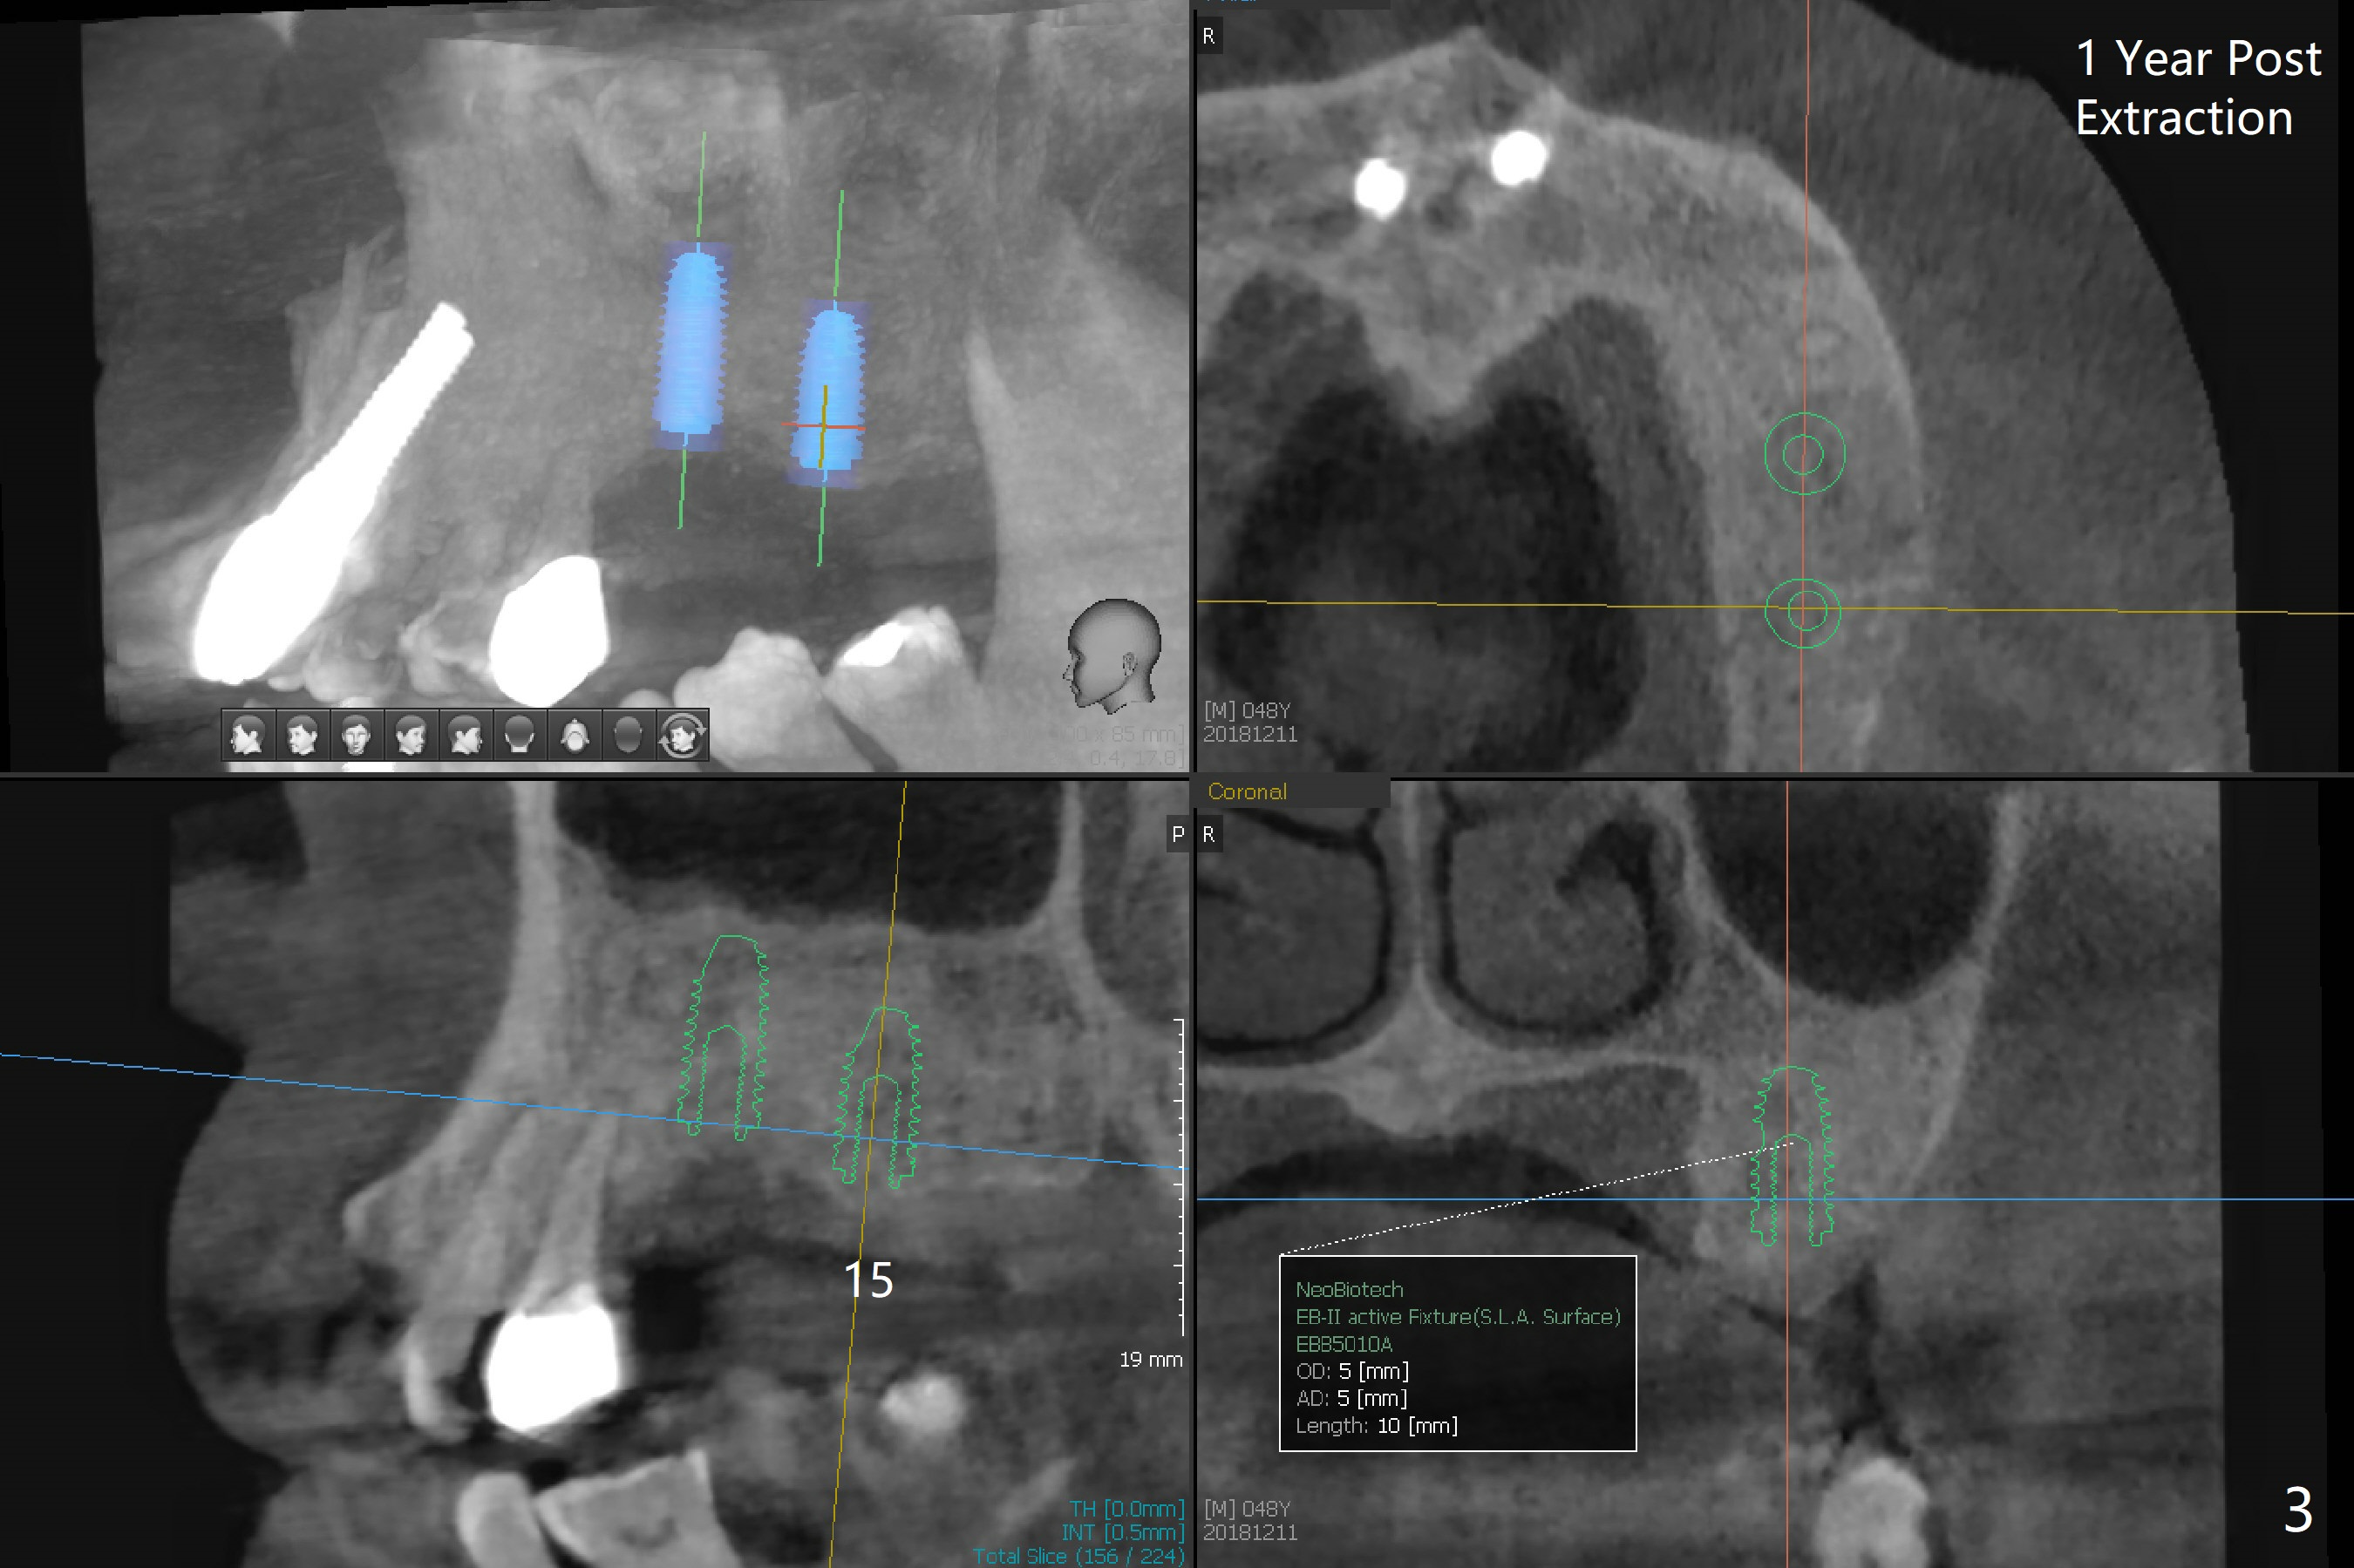

A 48-year-old man returns for implant placement at #14,15 and 29 (5 months post implant removal, 1 year post extraction and 2.5 months post implant removal, respectively, all with bone graft, Fig.1). Since the bone height at #14 and 15 is sufficient and sockets heal, implant placement will be done first (Fig.2,3), as compared to those at #29 (Fig.4). The tooth #18 is periodontally compromised with buccally cross bite (Fig.1); the position of the implant at #15 will be set up normally. When the site of #29 is ready for implant, use a large one (4.5 or 5x8.5 mm; use a dummy one as a tap).